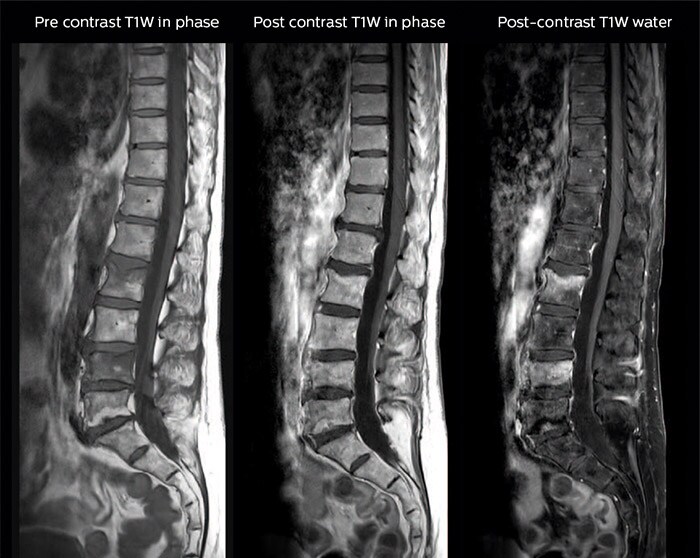

“В наших исследованиях позвоночника мы используем режим mDIXON TSE для сканирования пациентов с дегенеративными и воспалительными патологиями и переломами позвонков, а также для диагностирования вертебральных и паравертебральных опухолей, — говорит доктор Лефевр. — Этот режим позволяет получить за одно сканирование различные типы контрастов, что дает возможность визуализировать и диагностировать очаговые или диффузные поражения позвоночника.”

“Режим mDIXON TSE дает реальное преимущество в случаях острых и травматических повреждений позвоночника, позволяя сократить время сканирования и использовать только ограниченное число последовательностей. Для пациентов с болевым синдромом, которые, например, поступают из отделения неотложной помощи и нуждаются в хирургическом вмешательстве, МР-сканирование должно осуществляться очень быстро. За одно T2-взвешенное сканирование мы можем оценить спинной мозг, позвоночный диск и целостность связок по синфазным изображениям, а также трабекулярный перелом и отечные изменения по изображению воды.” Доктор Лефевр приводит другие примеры часто встречающихся заболеваний позвоночника, при которых предпочтительно использовать режим mDIXON. «В случае, например, грыжи межпозвонкового диска или дегенеративного заболевания межпозвонковых дисков нам не нужно выбирать между изображениями с подавлением или без подавления сигнала от жира. По синфазным изображениям, полученным с помощью Т2-взвешенных последовательностей, мы можем оценить анатомические изменения в замыкательной пластинке, а на изображении воды, полученном в ходе того же сканирования, мы видим воспалительные изменения.”